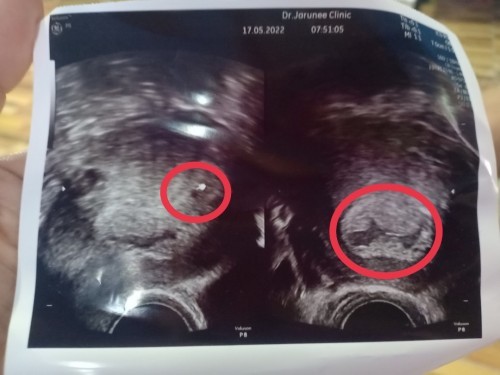

เราไปซาวช่องท้องมาเมื่อวันที่ 17 พค 65 หมอบอกว่า ถุงน้ำขรุขระไม่สวยเหมือนเป็นการตั้งครรภ์ผิดปกติ แต่ก็เจอจุดอีกจุดหนึ่ง ซึ่งมันเล็กมากเหมือนอายุครรภ์แค่ 4 สัปดาห์ แต่ถ้านับตาม ปจด ที่มาวันแรกก่อนท้อง จนตอนนี้คือ 7 สัปดาห์ มีใครเคยไปตรวจแล้วเป็นแบบเราบ้างไหมคะ และคุณหมอนัดซาวอีก 1 อาทิตย์เพื่อตรวจติดตามค่ะ